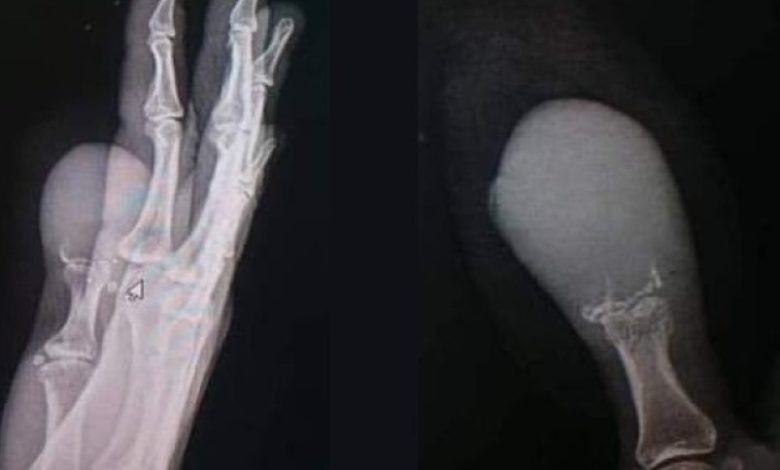

وأخيراً، راجعت المريضة العيادة الجلدية في مستشفى حماة الوطني، حيث أجريت لها صورة شعاعية ولوحظ من خلال الصورة وجود انحلال على مستوى السلامية البعيدة للإبهام، فتم أخذ خزعة استقصائية من الآفة للدراسة، وتم تشخيص حالتها بأنها “ميلانوما لاميلانينية، وهي آفة مبهمة غير مستجيبة لأي علاج مع انحلال بالسلامية البعيدة للظفر، مع احتمال كونها إصابة خبيثة”.